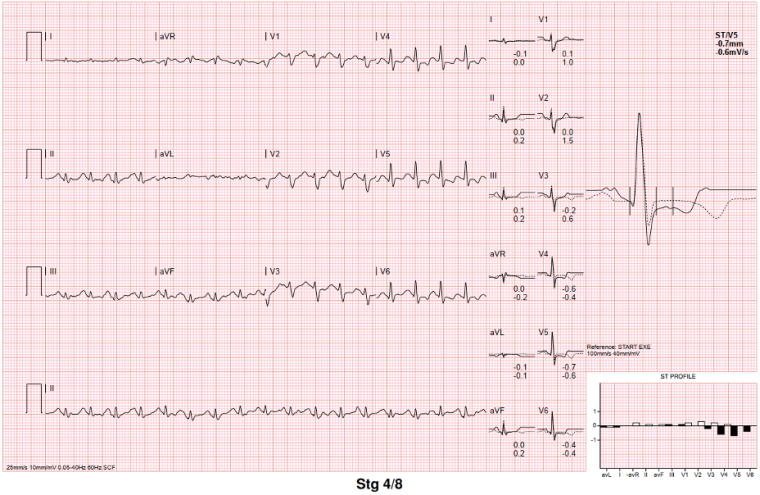

In the emergency department, a physical examination was undertaken, which was unremarkable, and given the episode of syncope, an ECG was performed (figure 2).

The baseline ECG as presented above prompted referral to a paediatric cardiologist, who 3 months later repeated an ECG and performed a baseline echocardiogram. This revealed borderline normal left ventricular (LV) size (LVEDD 51mm, z-1.7 LVESD 41mm, z+2.1), with slight thinning of the LV walls, moderate LV systolic dysfunction (LVEF by biplane 40%). The valvular appearances, coronary arteries and the right ventricular size and function were normal. The patient was commenced on lisinopril due to her systolic dysfunction.

This patient presented to a local pediatric emergency department with a primary complaint of continued vomiting. Through a thorough history of presenting complaint, the clinicians identified the brief episode of syncope, and although it was likely vasovagal in nature, they elected to perform an ECG. They subsequently identified the repolarisation abnormalities and appropriately referred the patient to a cardiologist. This highlights the importance of the ‘patient pathway’, as at times, the clinical presentation may be inconspicuous, and at a young age, and so thorough baseline investigations at a primary and secondary care setting with a “cardiomyopathy mindset” are crucial, as is the ability to correctly identify ‘red-flag’ signs, such as lateral repolarisation abnormalities on baseline ECG, to prompt secondary investigations.